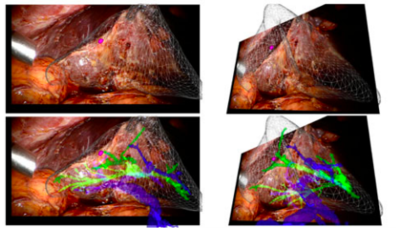

6.6. Results

The device clearly recognizes the marker, determines the position, scale and orientation of the model with respect to the camera and displays it. The accuracy of image registration was subjectively evaluated by checking the alignment of visible structures, by increasing and decreasing the degree of transparency of the superimposed virtual model. Figure 40 shows the result of the first experience.

Draft Samper 627449012-image49.png

From figure 40 it is observed that in the first experience there was a slight error in the alignment. This was due to an incorrect scaling of the marker and the model in Unity. After several experiences, this was corrected and the final results can be seen in figure 41- From the image, we can see that the AR system delivers a good accuracy, and the purple model completely covers the liver model's surface, with and without the top part of the model. Since the model comes from the CT scan of the exemplar, the virtual and real objects can completely be registered to each other. It is also observable that the display is a translucent system, allowing the user to view both the real and virtual worlds.

Draft Samper 627449012-image50.png

Figure 41. Final results

From Figure 41 it can be concluded that the AR setup is successful as the location of the tumor and vasculature can be correctly determined. It must be added that after the first experiences, three further improvements were made to the Unity project:

To sum up, the results clearly demonstrate that the location of the tumor and vasculature can be determined using the AR setup developed. These results can be categorized as significant as they suggest that AR could assist the accurate identification and resection of tumors during open hepatic surgeries.